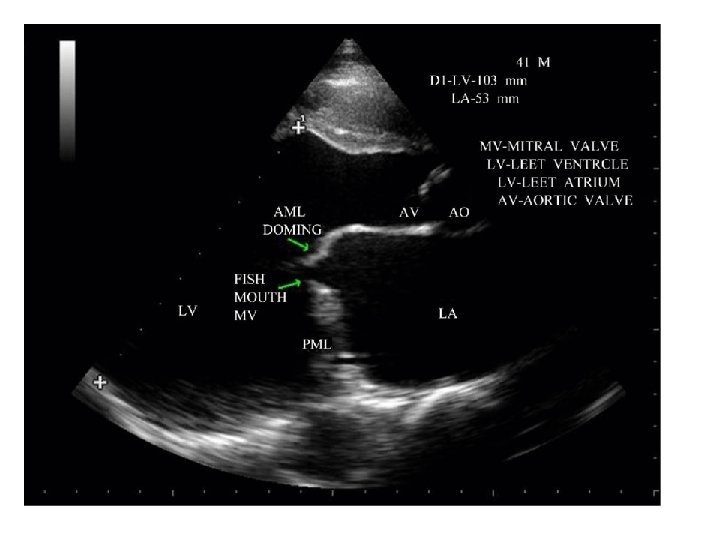

Investigations –Echocardiogram • Transthoracic echocardiography – To determine L/ R/ atrial and ventricular size – The sevirity of MS • Transoesophageal Echocardiography (TOE) – To detect the presence of L/ atrial thrombus JMJ 23

Investigations • Echo – – Thickened immobile cusps Reduced valve area Reduced rate of diastolic filling of LV Enlarged LA • Doppler echocardiography - definitive evaluation – Pressure gradient across mitral valve – Pulmonary artery pressure – Left ventricular function • Cardiac catheterisation - assessment of coexisting conditions. – Coronary artery disease – Mitral stenosis and regurgitation – Pulmonary artery pressure

Diagnosis ECG Tall R-waves (V 1 -V 3) RV hypertrophy P mitrale or atrial fibrillation Imaging X-ray (chest) Enlarged LA & appendage Signs of pulmonary venous congestion Echocardiography Thickened immobile cusps Reduced valve area Enlarged LA ↓ LV diastolic filling Doppler (DEFINITIVE) Pressure gradient across mitral valve Pulmonary artery pressure Left ventricular function Cardiac catheterisation

Complications Hemoptysis, pulmonary embolism, pulmonary infection, systemic embolization; endocarditis is uncommon in pure MS. Laboratory ECG Typically shows atrial fibrillation (AF) or left atrial (LA) enlargement when sinus rhythm is present. Right-axis deviation and RV hypertrophy in the presence of pulmonary hypertension. CXR Shows LA and RV enlargement and Kerley B lines. Echocardiogram Most useful noninvasive test; shows reduced separation, calcification and thickening of valve leaflets and subvalvular apparatus, and LA enlargement. Doppler flow recordings provide estimation of transvalvular gradient, mitral valve area, and degree of pulmonary